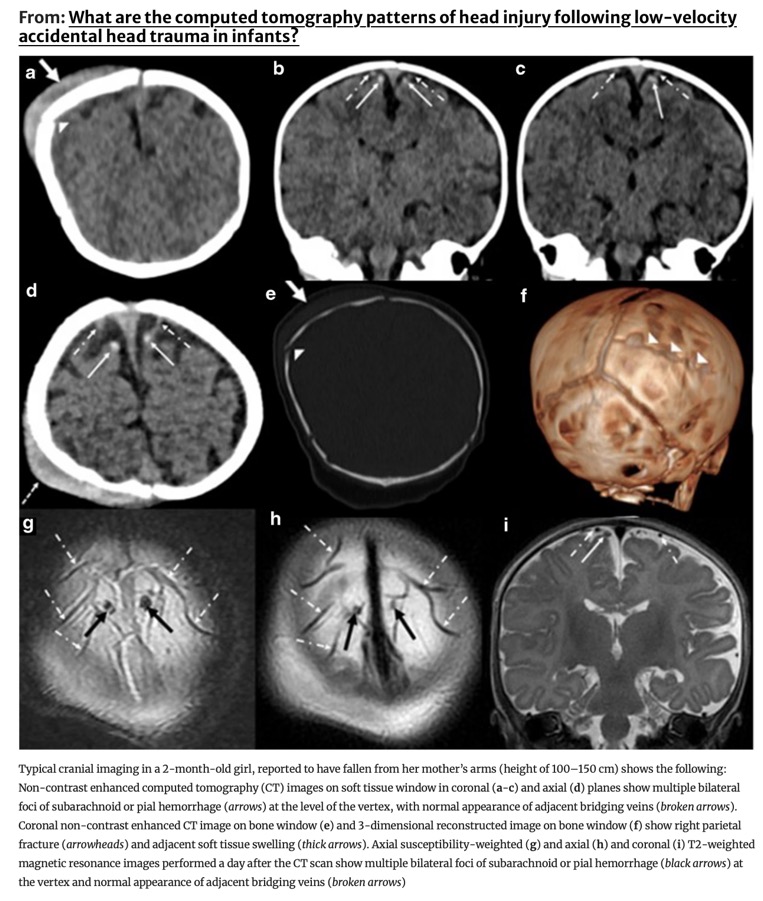

Modèles de lésions crâniennes par trauma à basse vitesse chez les nourrissons